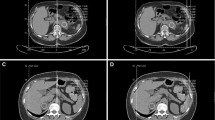

The CT images were loaded into an Advantage Windows workstation supplied by a CT vendor. The evaluation included the measurement of three dimensions of each lesion and hand traced slice by slice extraction of the volume of interest (VOI) inside a lesion covering as large a part of the soft tissue volume as possible while avoiding the edges and any necrotic parts of a lesion. The mean attenuation and standard deviation (SD) of the HU values were recorded, as was the fraction (%) of voxels with attenuation < 0 HU in a histogram using the “Volume Histogram” tool (Fig. 2). Splenic tissue is often used as a reference for adrenal tissue [7, 8]; therefore, a VOI similar to an adrenal mass was drawn inside a central part of the spleen to obtain the mean attenuation, SD and percentage of negative voxels as a reference. These measurements were performed in all lesions and spleen using three different slice thickness values (5 mm, 2.5 mm, and 1.25 mm). The analysis was performed by PK (1 year of experience) and PS (5 years of experience), discrepancies were resolved by FČ (15 years of experience); all three radiologists were blinded in respect to the final diagnosis.

A bar graph summarizing differences of mean attenuation, standard deviation of HU values, and percentage of negative voxels between three different options of slice thickness. Whereas mean attenuation shows no difference, SD and percentage of negative voxels reveal significant increase with thinner slice thickness in all three groups